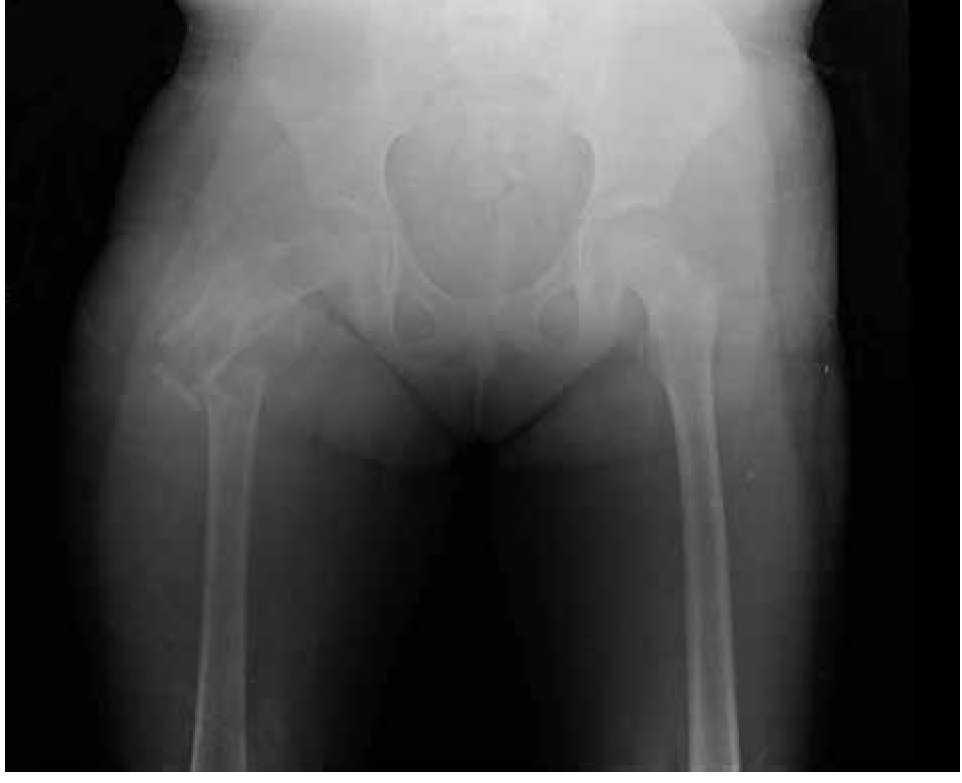

Paciente femenina, quien a los seis años ocho meses de edad, presentó aumento progresivo de volumen, dolor y limitación funcional del tercio proximal del muslo derecho en diciembre de 2007. La radiografía simple de fémur derecho al ingreso mostró una lesión osteolítica, metafisiaria, radiolúcida y con bordes mal definidos, sin afección de la cortical localizada en el tercio proximal del fémur derecho (Figura 1). Se realizó tratamiento con legrado óseo y colocación de injerto óseo, con mejoría de sus condiciones clínicas. En la biopsia se realizó diagnóstico de QOA de tercio proximal de fémur derecho. Dos años después la paciente acude nuevamente por dolor localizado en extremidad pélvica derecha y en la radiografía se observó una fractura de tercio proximal de fémur, resorción del injerto y destrucción de la cabeza femoral y del tercio proximal de la diáfisis (Figura 2), colocándose clavo intramedular. Siete meses después presentó aumento de volumen de muslo derecho y dolor. Se realizó exploración quirúrgica con toma de biopsia de la cabeza femoral y de la diáfisis, así como drenaje de hematoma (1 500 mL). En esta segunda biopsia se aprecia en la mayoría de los fragmentos, septos fibrosos rodeados por hemorragia, células gigantes multinucleadas y hueso de neoformación concluyentes de QOA con áreas focales hipercelulares con atipias con un Ki67 del 50% y un p53 de 20%, por lo que se sugirió la posibilidad de malignidad (Figura 3). De forma retrospectiva y conociendo la existencia de una lesión radiológica e histológica probablemente maligna, se revisó de forma intencionada el material de la biopsia original del diagnóstico de QOA, encontrándose aisladas células atípicas con un índice de proliferación de 30% y positividad focal a p53. (Figura 4). En la imagen por resonancia magnética (RM) se observó lesión de tercio proximal de fémur, dependiente de la cortical, con reacción perióstica e involucro de tejidos blandos, que abarcaba hasta la unión del tercio medio con el tercio proximal (Figura 5). Se realizó una tercera biopsia guiada por tomografía axial computarizada (TAC), confirmando la presencia de sarcoma osteogénico. En la evaluación de la búsqueda de metástasis, se observó presencia de nódulo pulmonar basal izquierdo de 7 mm que ha permanecido sin cambios hasta el momento actual. Inició tratamiento con quimioterapia neoadyuvante con cisplatino (120 mg/m2) y doxorrubicina (75 mg/m2) por dos cursos, presentando posterior a los mismos, progresión local de la enfermedad por lo que se intensificó tratamiento sistémico con ciclofosfamida a dosis escalas (iniciando con 300 mg/m2/dosis por seis, aumentando 50 mg/m2/dosis en cada curso) y etopósido (200 mg/m2/día por tres días) durante cuatro cursos, y se realizó amputación de extremidad. El producto de la amputación mostró un tumor con cavidades llenas de sangre limitadas por delgadas láminas de hueso (Figura 6A). Histológicamente, se aprecian septos limitados por células pleomórficas de aspecto neoplásico. Hay áreas de formación de osteoide. El diagnóstico histopatológico fue de OT con 10% de necrosis tumoral posquimioterapia con invasión a tejidos blandos (Figura 6B y 6C). Posteriormente se administró quimioterapia con altas dosis de metotrexate (12 g/m2/dosis semanal por tres) más ifosfamida (3 g/m2/día por cinco) y doxorrubicina (75 mg/m2/dosis) por tres cursos. Se envió a vigilancia en noviembre de 2011 y actualmente se encuentra en remisión completa de la enfermedad.

Figura 1. Radiografía antero-posterior de fémur derecho con quiste óseo aneurismático.